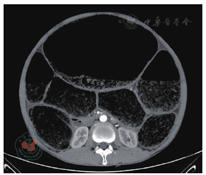

患者男性,46岁,因"反复腹胀腹痛伴排便不畅1个月,加重伴呕吐3天"于2017年7月20日急诊入院。患者于1个月前因腹胀腹痛伴排便不畅于外院就诊,予以导泻、灌肠等处理症状好转,后患者仍间断出现腹胀伴腹痛,均于外院对症治疗,3天前患者腹痛腹胀症状较前加重并恶心呕吐,查腹部立位平片示:肠梗阻。外院予保守治疗3天后症状无缓解,遂急诊转至苏州大学附属第一医院。患者主诉患有"便秘"数年,自服泻药均可通便,无其他特殊药物服用史,近期工作劳累,精神压力较大,否认毒物、放射性物质接触史,无外伤手术史。入院查体:急性痛苦面容,全腹膨隆,未见胃肠型及蠕动波,全腹压痛明显,有反跳痛、肌紧张,腹部叩诊鼓音,移动性浊音(-),肠鸣音弱,1~2 b/m。直肠指检:胸膝位,肛门无痔块脱出,无肛裂,指检未及肿块,指套无染血。腹部CT(平扫+增强):全结肠普遍扩张,乙状结肠高密度影,考虑粪便(图1)。以"巨结肠伴梗阻、急性腹膜炎"收治入院,急诊行剖腹探查术。术中见:腹腔中等量清亮腹腔积液,空肠无扩张,回肠稍扩张,升结肠、横结肠、降结肠以及乙状结肠明显扩张、冗长,最大直径约15 cm,其中以乙状结肠扩张尤为严重(图2),结肠内充满干结大便,质硬,术中行直肠指诊未触及肿块。遂行结肠次全切除术+末端回肠造口术。术后病理:(次全结肠)肠壁黏膜慢性炎,肌壁间可见神经元,浆膜面局灶见中性粒细胞浸润,部分血管充血,阑尾慢性炎(图3)。患者术后4天半流质饮食,术后10天出院。术后2个月随访,患者体重较前增加10 kg。于2017年10月31日行"造口回纳(回肠直肠吻合术)"。患者回肠直肠吻合术后出现腹泻症状,经药物治疗后,每天排便可控制在3次以内。